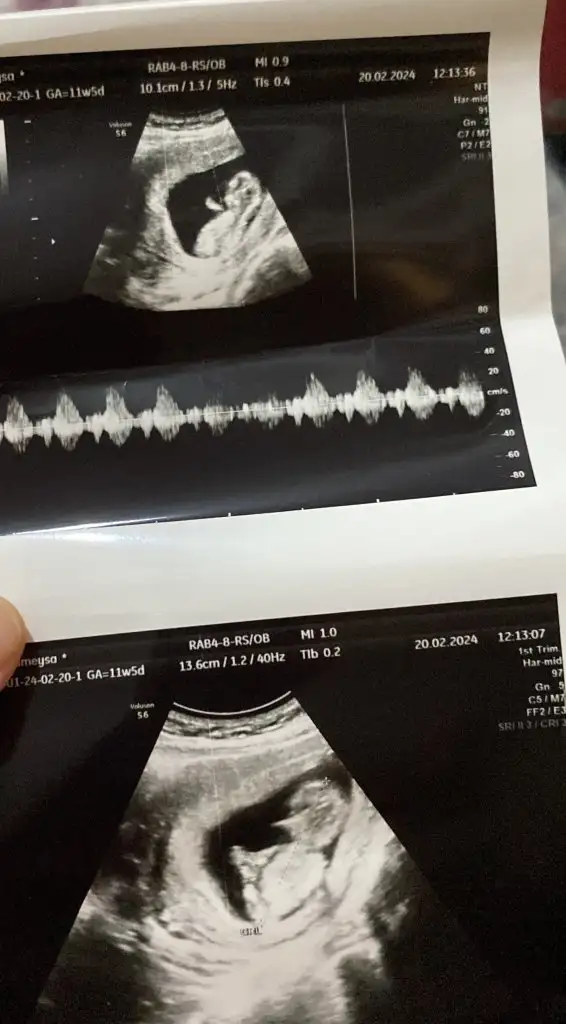

11 haftalık banada tahminde bulunabilir misiniz guzel anneler sağlıklı olması tabiki önceliğimiz ama merak iste 😍